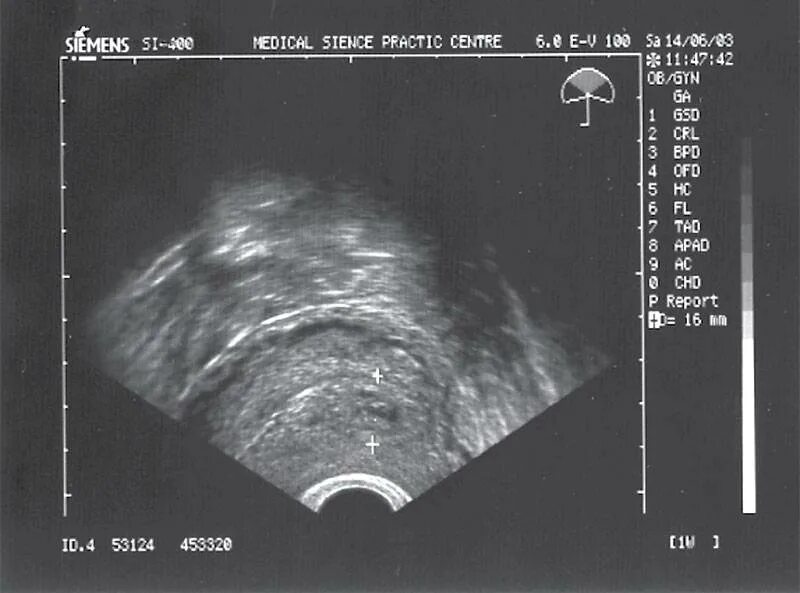

Как называется узи на ранних сроках